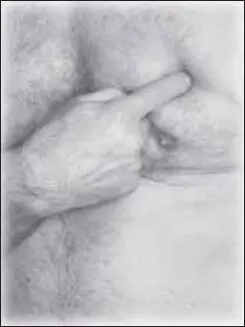

Завершать массаж необходимо воздействием на точку хэ-гу на стороне заложенной ноздри (точка расположена на тыльной стороне кисти; при сжатии 1-го и 2-го пальцев образуется возвышение, где находится искомая точка) (рис. 128). Воздействие стимулирующее, тонизирующее (до 30–40 секунд).